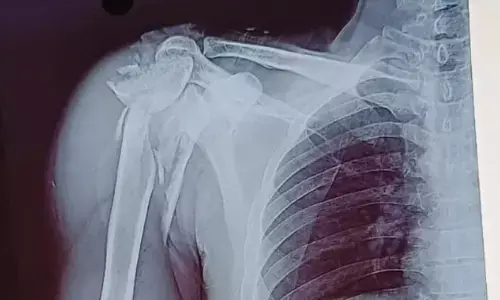

Chhindwara News: सिम्स में सफल ऑपरेशन, मरीज के कंधे की बुरी तरह चूरा हड्डियों को दोबारा जोड़ा

- By Bhaskar Hindi 19 Oct 2024 4:34 PM IST